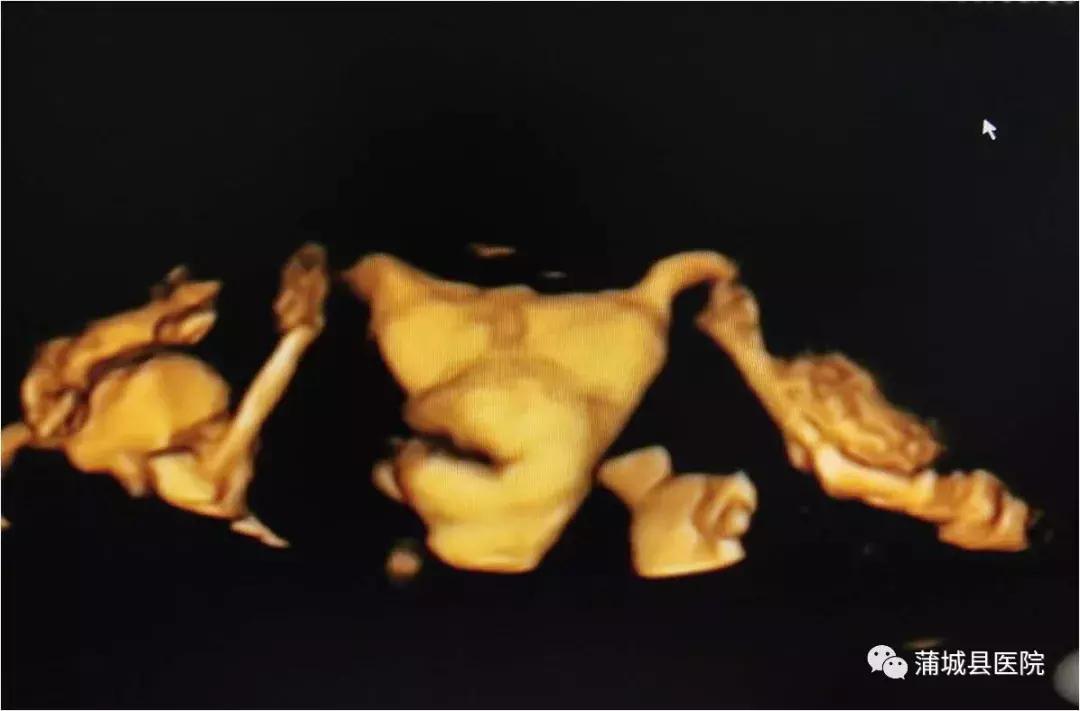

蒲城县医院超声科引进的 美国GEVolusonE8彩色多普勒超声仪和超声造影剂六氟化硫微泡(声诺维),可以用于三维/四维子宫输卵管超声造影检查。超声输卵管造影术是通过向宫腔注入造影剂后,使原本闭合的宫腔和输卵管扩张,然后进行三维成像,主要用于评价输卵管通畅性和诊断子宫宫腔病变。由于子宫输卵管超声造影和三维超声的完美结合,超声声像图的质量得到明显改善,并可获得更多的信息,使诊断的敏感性和特异性显著提高。

输卵管超声造影术具有实时、空间感强、无辐射等优势,造影剂(六氟化硫微泡)具有良好的安全性和耐受性,副作用发生率低,用量小,可溶解在血液中随呼吸排出。

三维/四维超声输卵管造影,能够快速、准确地评估输卵管的通畅性,是筛查输卵管通畅性的有效手段。